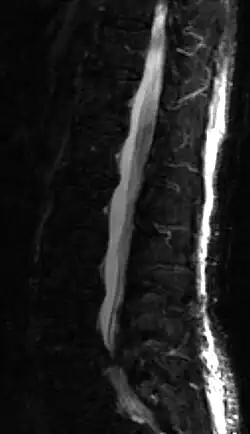

MRT-Darstellung eines Bandscheibenvorfalles

Der Spinalkanal erscheint in dieser Auswertungstechnik hell, die von links kommende, dunkle Vorwölbung ist der Vorfall, der den Spinalkanal abklemmt.

Ein Bandscheibenvorfall kann mittels MRT diagnostiziert werden. Als alternatives Verfahren kann ein Bandscheibenvorfall auch mittels CT festgestellt werden, die jedoch aufgrund der Strahlenbelastung und des schlechteren Weichteilkontrastes Nachteile gegenüber einem MRT hat. Ein älteres Verfahren, das besonders vor der Einführung von MRT- und CT-Geräten verwendet wurde, aber auch heute noch Einsatz bei besonderen neurologischen Fragestellungen oder Kontraindikationen zu einer MRT-Untersuchung findet, ist die Myelographie. Hierbei wird ein Kontrastmittel in den Liquorraum gespritzt.